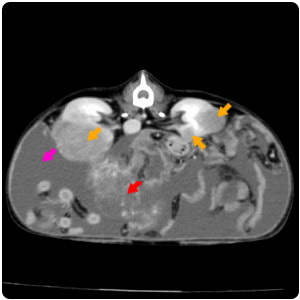

| 腹腔腫塊(紅)、腹水(黃) |

腹水(紫)、腹部腫塊(紅)、子宮殘段(黃) |